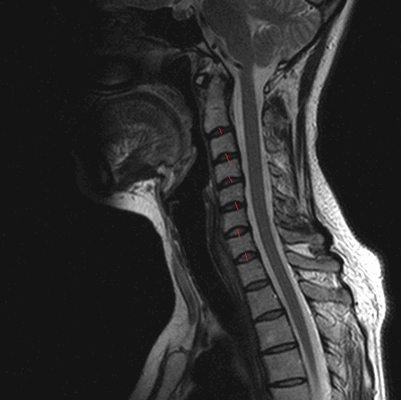

МРТ шейного отдела позвоночника. Острая травма. Компрессия спинного мозга, отек и контузия. Сагиттальная Т2-взвешенная МРТ.

МРТ позвоночника в шейном отделе, оценка высоты дисков (указана красными линиями)